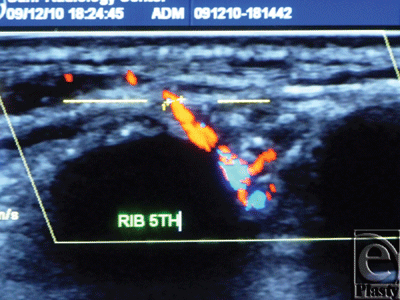

The site of the detectable perforator(s) was projected by a colored marker on the patient's skin so as to estimate the label remoteness (representing the perforation site) from the sternum (Fig 2), and the number of encountered perforators parasternally in each investigated space was counted as well. The inner diameter of each perforator was measured (Fig 3). Figures 4 to 8 show color duplex photos for perforators penetrating the fascia to reach the dermoglandular target.

| Figure 4. Color Duplex photo shows a 4th internal mammary artery perforator while perforating the superior surface of the pectoralis major muscle (the dashed line). |